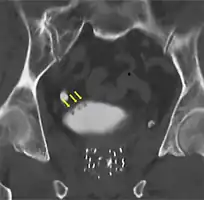

If invasive or high grade (includes carcinoma in situ) cancer is detected on TURBT, an MRI and/or CT scan of the abdomen and pelvis or urogram and CT chest or x-ray chest should be conducted for disease staging and to look for cancer spread (metastasis). Increase in alkaline phosphatase levels without evidence of liver disease should be evaluated for bone metastasis by a bone scan.[1] Although 18F-fluorodeoxyglucose (FDG)-positron emission tomography (PET)/CT has been explored as a viable method for staging, there is no consensus to support its role in routine clinical evaluations.[54]